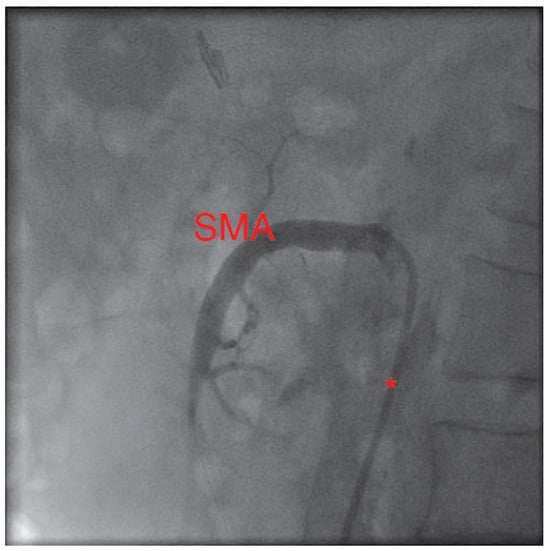

In a first step, the SMA was treated by balloon angioplasty and a bare metal stent (hippocampus 7.0/20 mm) was implanted. After 2 weeks, the patient was readmitted with improved but not completely resolved abdominal symptoms. The remaining stenosis of the CA was revascularised, using another bare metal stent (hippocampus 6.0/20 mm). During a clinical follow-up of six months, the patient was asymptomatic.

Figure 2. Same projection: again with a catheter (*) in place. After ballooning and stent implantation the stenosis is no longer visible.